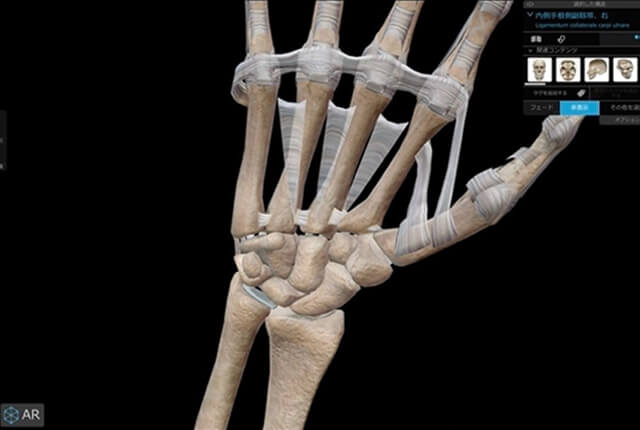

手関節の解剖

手関節は橈骨、尺骨、および8個の手根骨から成ります。

DRUJ、尺骨遠位、手根骨をつなぐ支持組織は三角線維軟骨複合体(TFCC)と言います。

三角線維軟骨複合体(TFCC)

TFCC部分切除術

neutralおよびminus variancで、DRUJ不安定性がない症例に適応がある手術法です。